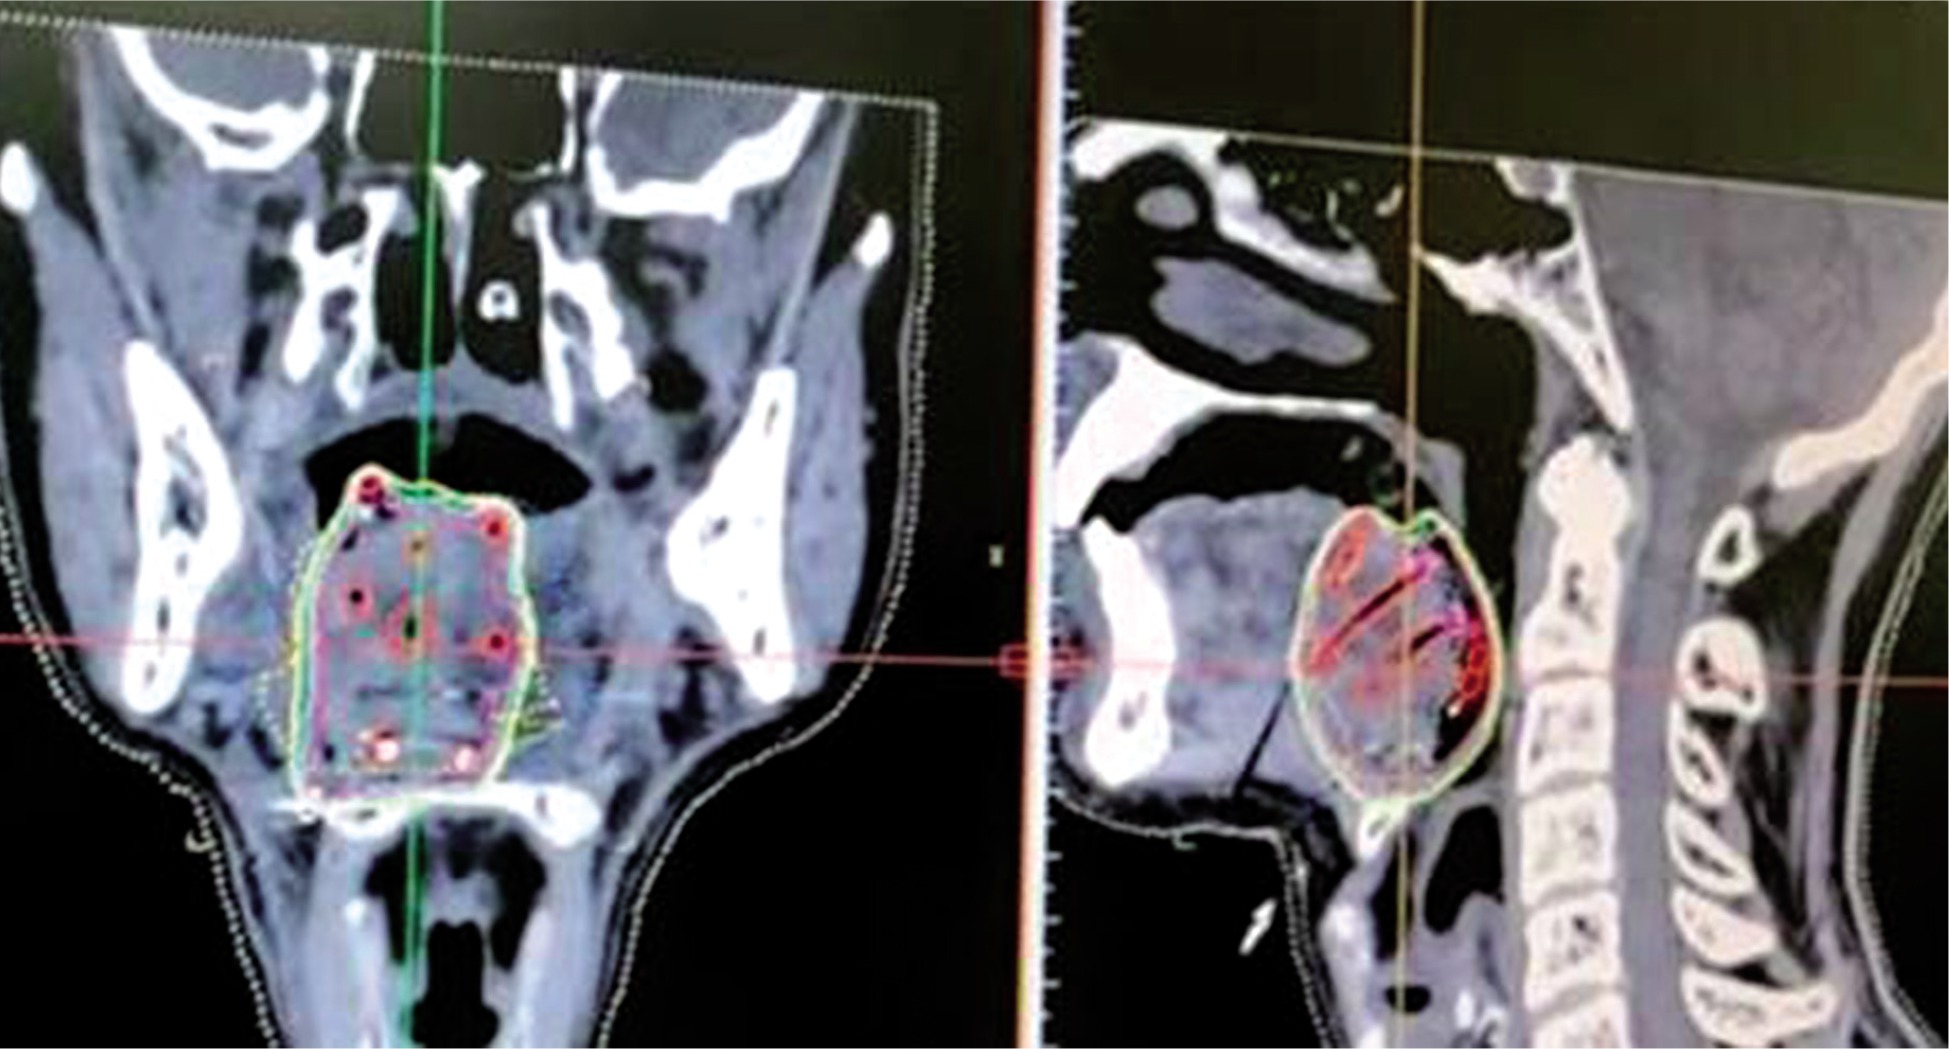

CT images taken with a slice thickness of 1-1.5 mm and transferred to the planning system for treatment planning (Figure 3).

Dummy wires placed within the catheters helps to identify the individual catheter in the images, and the catheters can be individually tracked.

Contouring of gross tumor volume (GTV)/clinical target volume (CTV) and critical organ at risk (OAR).

Generation of virtual irradiation plan from loading of virtual source with respect to CTV.

Evaluation of the isodose distribution from the generated plan and isodose line (dose-rate or prescription line) assessed, which encompasses desired CTV/internal target volume (ITV) without a cold or hot spot, providing dose inhomogeneity.